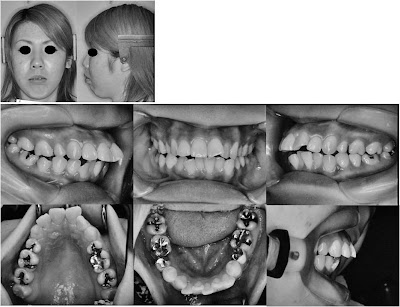

A correção de um grave protrusão maxilar em uma adulta com movimento distal dos molares superiores, era um dos mais difíceis problemas biomecânicos em ortodontia. Este artigo relata o tratamento de uma adulta com caso de grave protrusão maxilar e um grande sobressaliência, tratada com um sistema de ancoragem esquelética. Uma paciente do sexo feminino, idade 22 anos e 3 meses, queixou da dificuldade de vedamento lábial, devido à severa protusão maxilar com um sorriso gengival. Overjet e overbite foram de 7,6 mm e 0,9 mm, respectivamente.

Ela tinha um histórico de tratamento ortodôntico em que seus primeiros pré-molares superiores foram extraídos. No final do procedimento foi promovido uma movimentação distal dos molares superiores, mini placas de âncoragem foram colocadas no processo zigomático. Após atingir uma relação molar Classe I, retração e intrusão dos incisivos superiores foram realizadas. Depois de 2 anos de tratamento, uma oclusão aceitável foi alcançado com uma relação molar Classe I. perfil dela continuou convexo e a protrusão lábio superior foi consideravelmente melhorada, e os lábios mostrou menos tensão durante vedamento. Após 2 anos de um período de contenção, uma oclusão aceitável foi mantida sem recorrência de protusão maxilar, indicando uma estabilidade da oclusão.